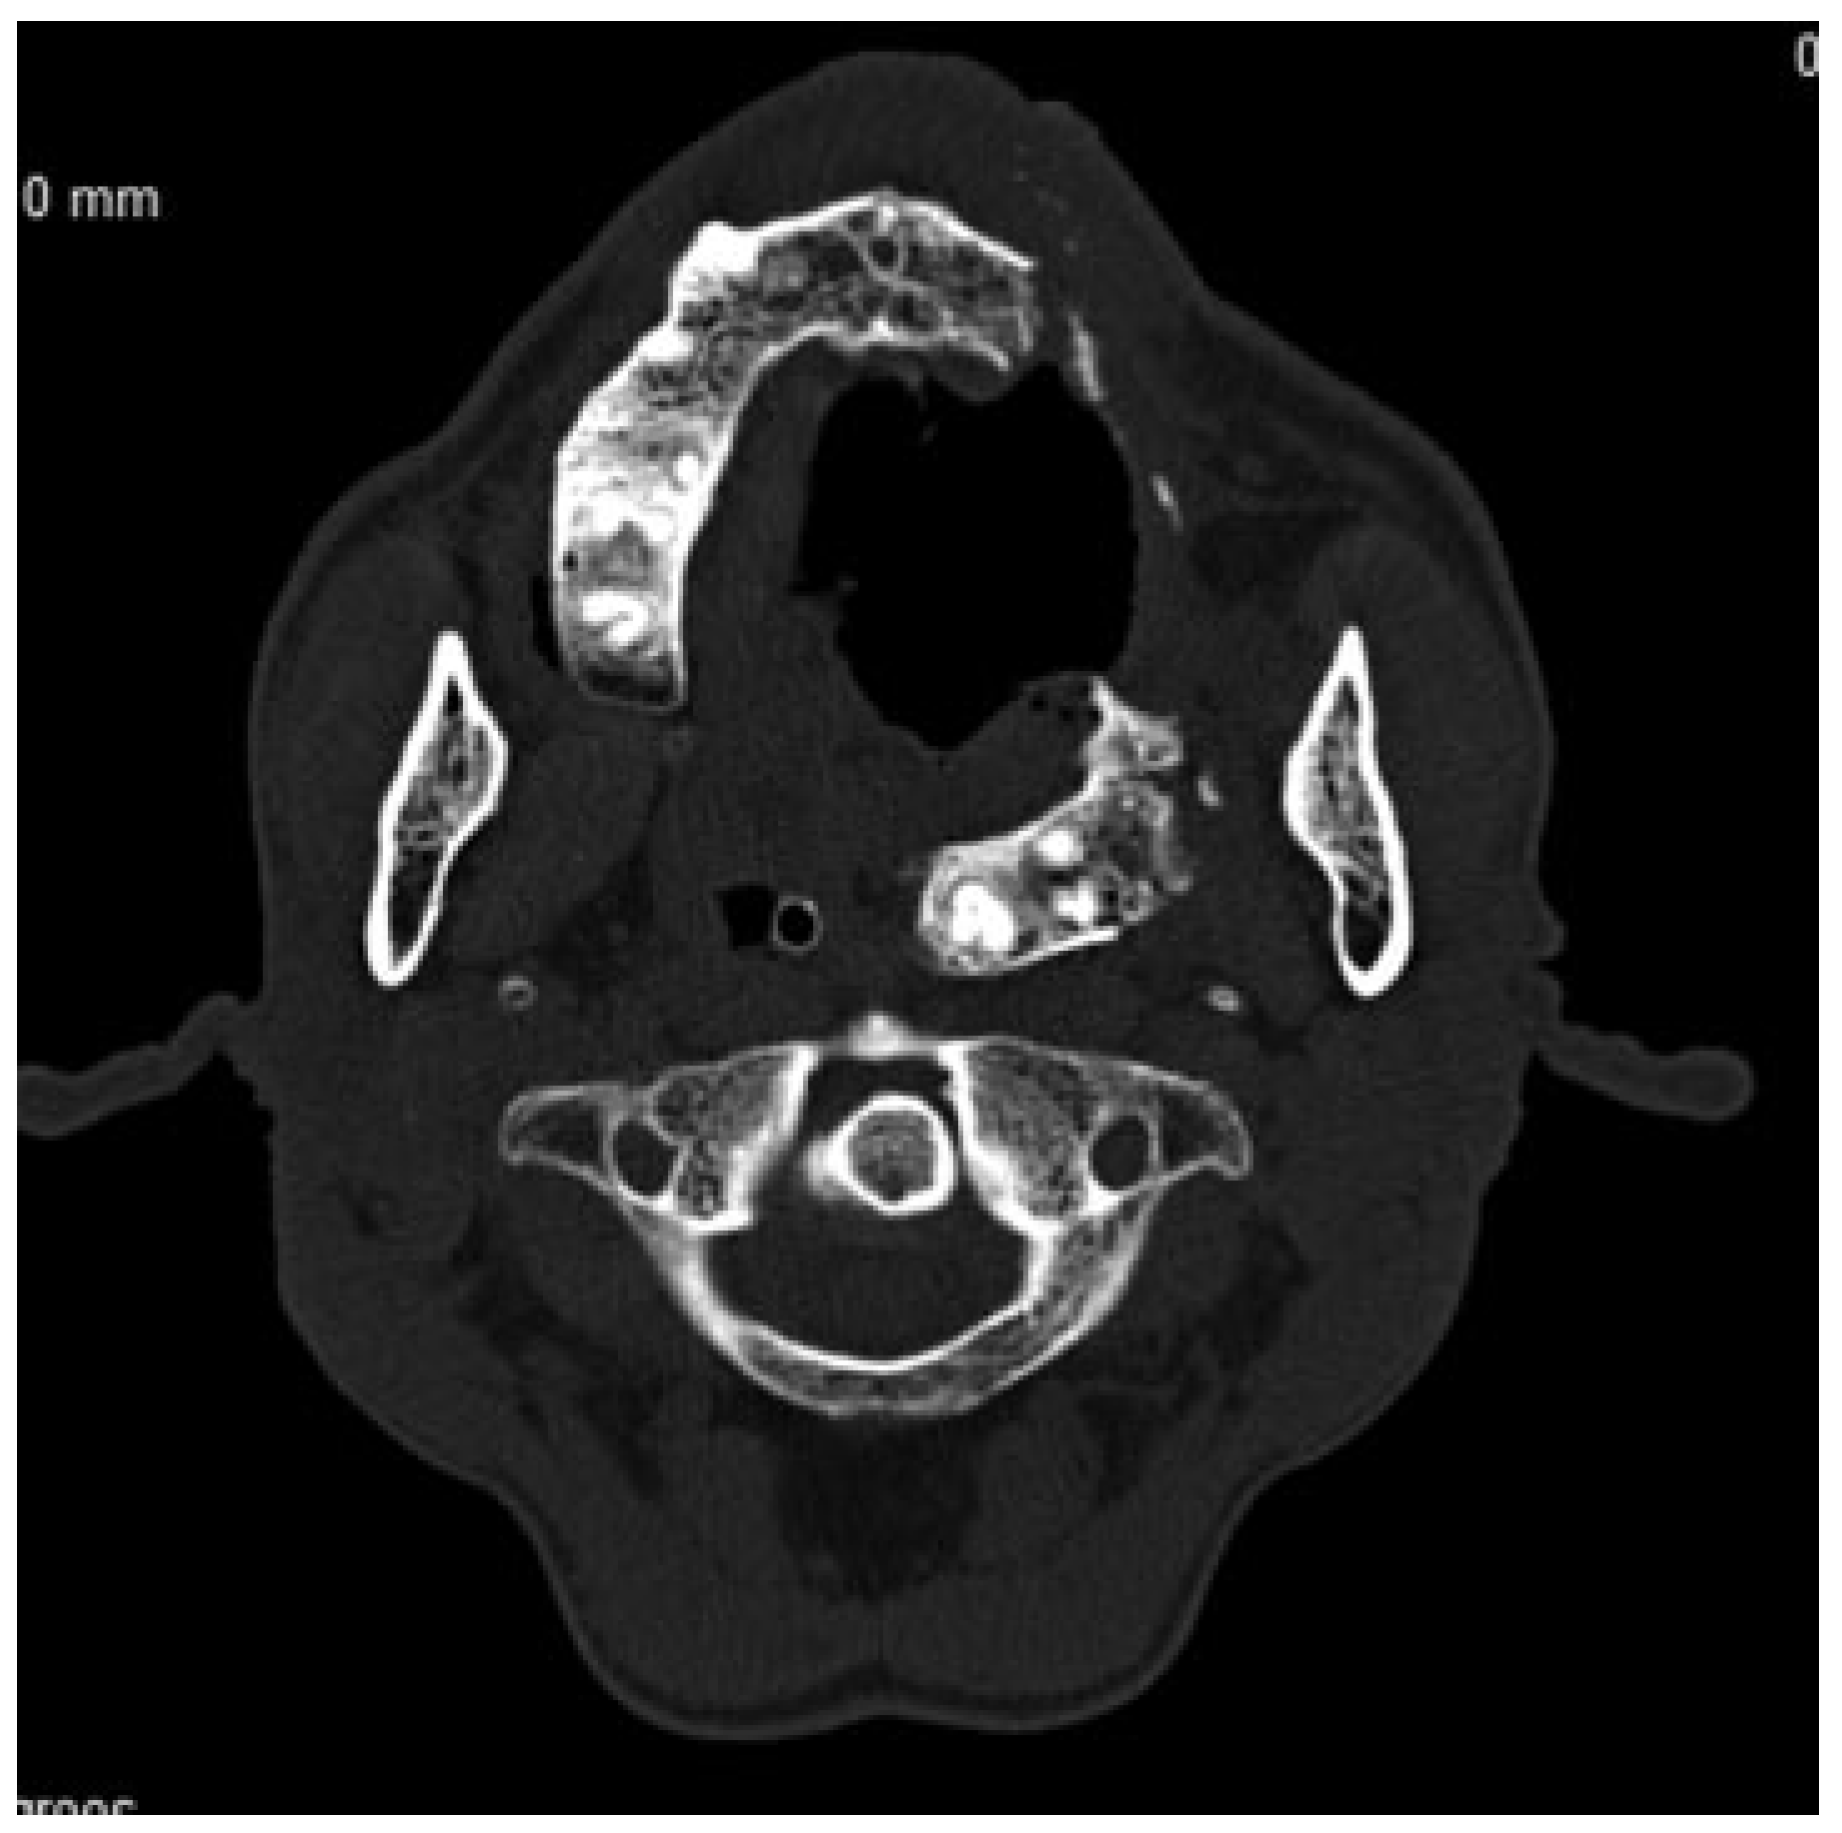

Figure 1.

Computerized tomographic scan showing displacement of fractured maxillary segment into lateral pharyngeal space.